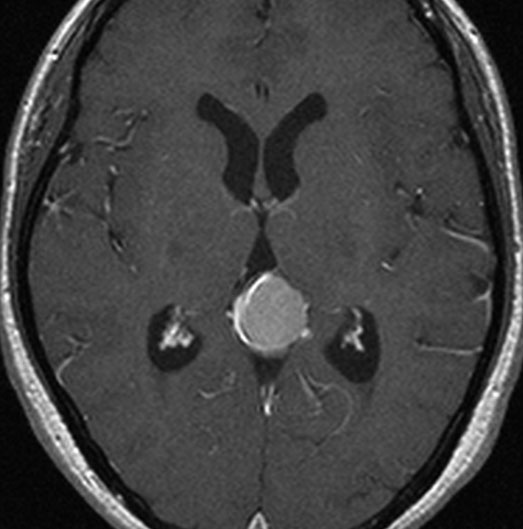

静脈洞交会髄膜腫 meningioma of the confluence of sinuses

若い女性に偶然発見されたものです。直静脈洞と静脈洞交会の接合部あたりに発生したもので,静脈洞はほぼ閉塞に近い所見でした。しかし,この部分の静脈洞は,テント硬静脈側副路が発達することがあるので,硬膜を含めた積極的な摘出をすることは絶対にできません。もしほんの少しでも流れがある直静脈洞を閉塞させると短時間に脳死になるような脳静脈圧亢進が生じる可能性があるからです。静脈洞内に少し取り残して(右下の矢印)手術を終了しました。手術後には定位放射線治療を行って再増大を防ぎます,